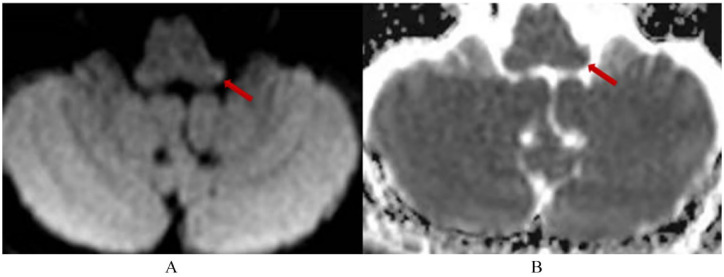

Case report: We report the case of a 65-year-old man who presented to the neurology department because of herpes zoster on the right trigeminal nerve distribution. At 12 hours after admission, he developed transient vertigo along with nausea and unsteady walking and left-sided spontaneous horizontal nystagmus, gaze-evoked nystagmus, and upbeat nystagmus. The other usual signs of LMI including Horner syndrome, dysarthria, swallowing difficulty, and hemibody sensory change were absent. Video head impulse indicated decreased head impulse gain of the vestibulo-ocular reflex for the bilateral horizontal, anterior, and posterior semicircular canals with abnormal saccade waves. Suppression head impulse paradigm showed few downward saccades reflecting anti-compensatory saccades after the end of the head impulse back to the head-fixed target and decreased vestibulo-ocular reflex gain values of bilateral semicircular canals. Brain magnetic resonance imaging (MRI) showed a small infarct in the far dorsolateral portion of the left rostral medulla. The cerebrospinal fluid was positive for VZV DNA.